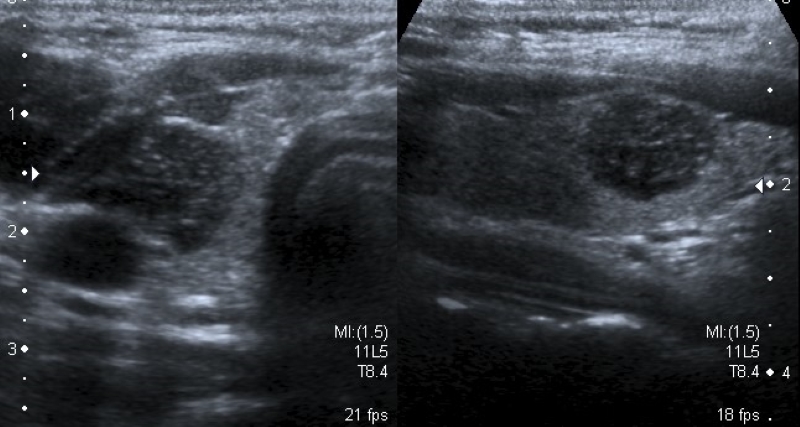

Composición

Describe el componente interno del nódulo, identificando la presencia de contenido sólido (Fig. 1) o quístico (Fig. 2), y en los casos de nódulos mixtos (Fig. 3) la proporción de cada uno (predominantemente sólido/ predominantemente quístico). Cuando se evalúa un nódulo parcialmente quístico es importante caracterizar su componente sólido indicando además si tiene localización central o periférica (esta última podría asociarse con mayor riesgo de malignidad)13.

Los nódulos completamente quísticos son considerados benignos2,14,15) y los sólidos se asocian mayormente a malignidad15,16, pero hay descriptos nódulos sólidos benignos, como así también nódulos confirmados como CPT con componente mixto2,15,17.

Existen otro tipo de nódulos, los espongiformes, que presentan un patrón mixto con múltiples quistes pequeños en su interior, y tienen un muy bajo riesgo de Malignidad2,13,14,18.